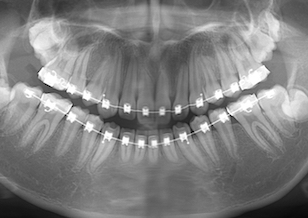

After Ⅲの写真は、治療中のパノラマレントゲン写真です。右側上顎第3大臼歯が右側上顎第2大臼歯に重なるように埋伏しています。左側上顎第3大臼歯と左側上顎第2大臼歯も埋伏していることが確認できます。